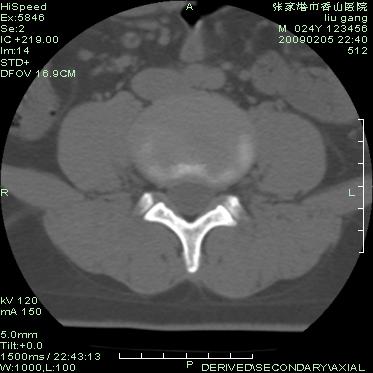

以下是引用随光逐影在2009-3-11 14:43:00的发言:[br]平片:l3、4、5及s1前上缘见类似“切角征”。[br]ct扫描:腰椎多个节段椎间盘向椎体内(椎体前部)突出。